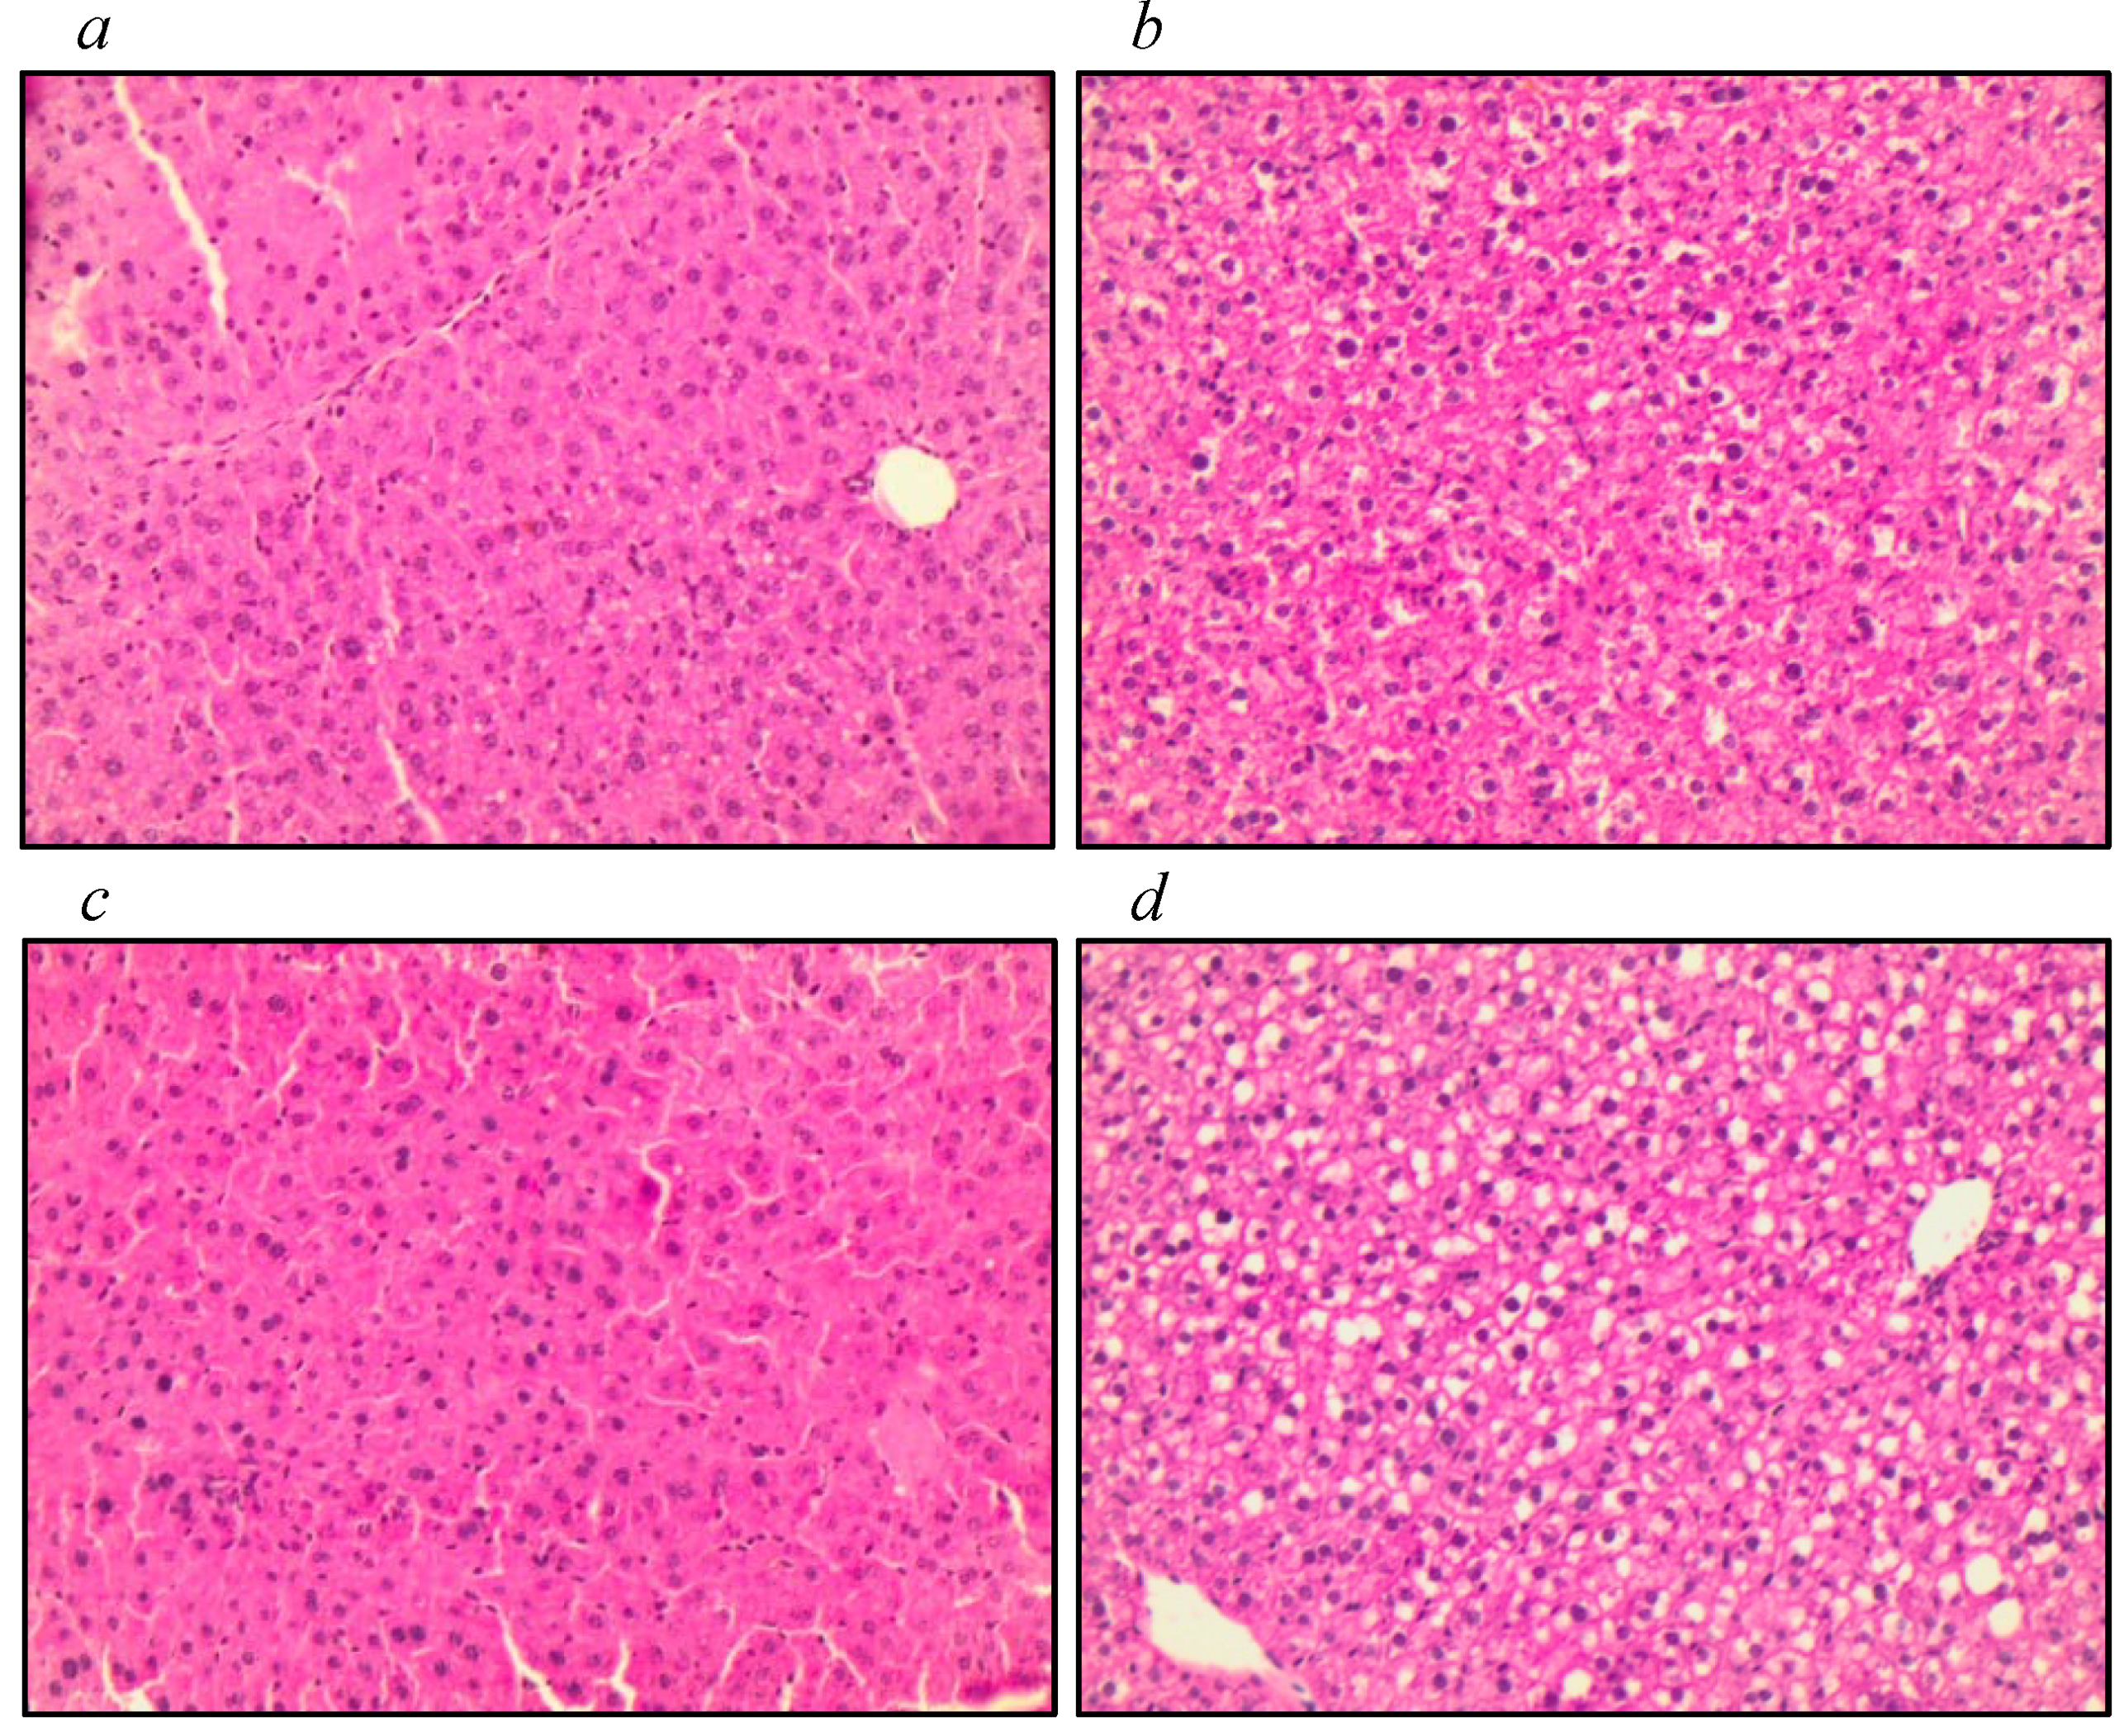

3.3. Assessment of Liver Tissue, Antioxidant Function, and Markers of Oxidative Stress

| (a) | |||||||||

| Variables | IL−10−/−+O3 | IL−10−/− | WT+O3 | WT | Kruskal-Wallis p-Value | ||||

| Median | IQR | Median | IQR | Median | IQR | Median | IQR | ||

| Scores | 1.0 | 0–1.0 | 3.0 | 1.50–3.0 | 1.0 | 0–10 | 2.0 | 0–3.0 | 0.009 * |

| (b) | |||||||||

| Bonferroni post-hoc test p-Value | |||||||||

| IL−10−/− vs. Il-10−/−+O3 | IL−10−/− vs. WT | IL−10−/− vs. WT-03 | IL−10−/−+O3 vs. WT | IL−10−/−+O3 vs. WT+03 | WT vs. WT+O3 | ||||

| Scores | 0.017 * | 0.260 | 0.017 * | >0.999 | >0.999 | >0.999 | |||